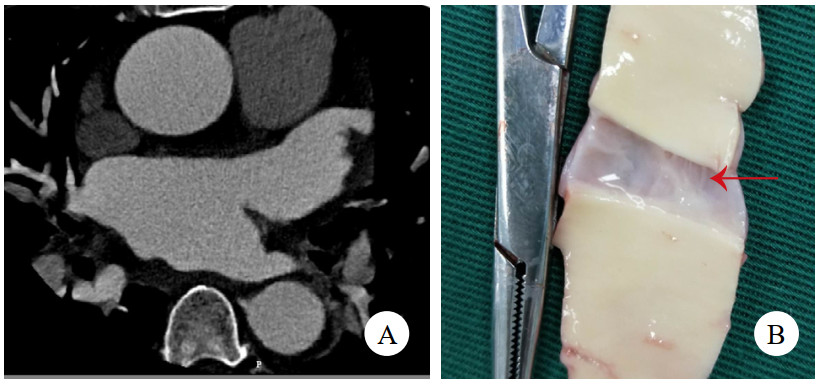

病例4,男,63岁,因“活动后胸闷、气促6年,加重1月”入院。TTE提示二尖瓣前叶A2区腱索断裂伴脱垂、重度返流,主动脉瓣重度返流,三尖瓣中度返流,左心室显著增大,左心室舒张末期直径86 mm,心功能减低,中重度肺动脉高压,升主动脉内径增宽直径43 mm。冠状动脉CTA提示双侧冠状动脉无显著病变,少量心包积液,未见主动脉根部病变(图 4A)。术前准备后,择期手术,术中见主动脉前壁窦管交界水平一长约2 cm的内膜撕裂符合LIT。仔细观察切除标本(图 4B),见内膜裂口边缘光滑,考虑为陈旧性改变。予行Bentall加二尖瓣机械瓣置换加三尖瓣成型术。术后康复顺利,规律抗凝随访1年。

| 注:A为冠状动脉CTA,未见异常;B为切除的主动脉壁,箭头示内膜裂口 图 4 例4患者CT影像及主动脉壁照片 |